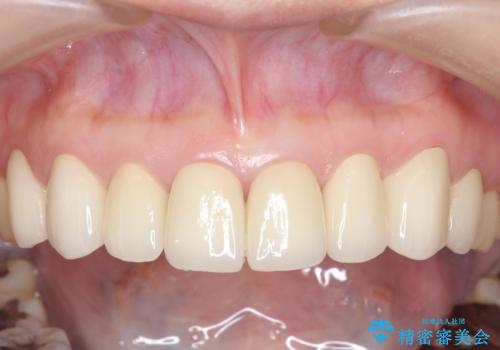

上顎は左4番から右4番までの8歯、下顎は左3番から右3番までの6歯、計14歯をオールセラミッククラウンにより補綴しました。

今回用いたオールセラミッククラウンはジルコニアフレームという白い素材の上にセラミックを盛っているため、審美性が非常に高いのが特徴です。

また、ジルコニアは人工ダイヤモンドの材料にも使われているほど高い強度を持っており、そのためオールセラミッククラウンは審美性だけでなく、奥歯やブリッジの補綴も可能とするクラウンです。